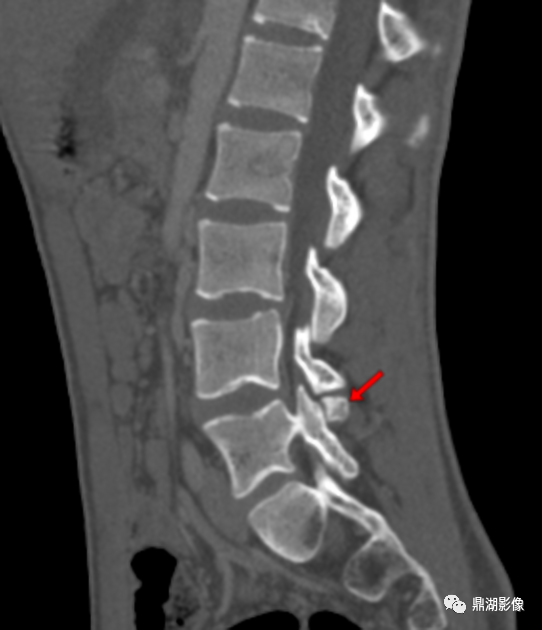

男性患者,40岁,腰背部疼痛,否认外伤史。

奥本海默小骨(Oppenheimer ossicle)

影像学特征:奥本海默小骨具有光整的骨皮质,相邻小关节的滑膜囊可与奥本海默小骨与关节突之间的裂隙相通。

在影像学上,需与关节突骨折相鉴别:奥本海默小骨形态规则、骨皮质光整、连续。